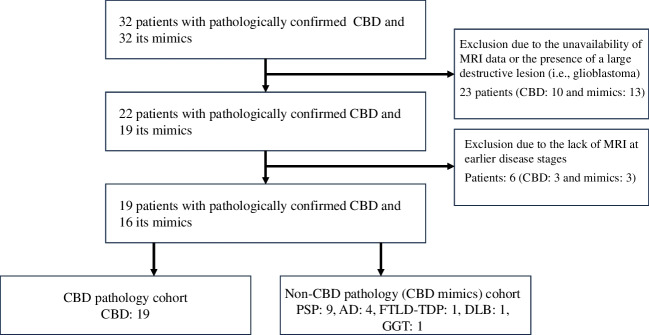

First, 10 patients with CBD and 12 patients with CBD mimics were excluded from the J-VAC study cohort due to the unavailability of MRI data and the presence of large destructive lesions. Additionally, one patient with CBD mimics comorbid with glioblastoma was excluded. Second, three patients with CBD and three patients with CBD mimics were also excluded as only MRI data at the advanced stage were available. Ultimately, the study included a total of 19 patients with CBD and 16 patients with CBD mimics (Fig. 4).